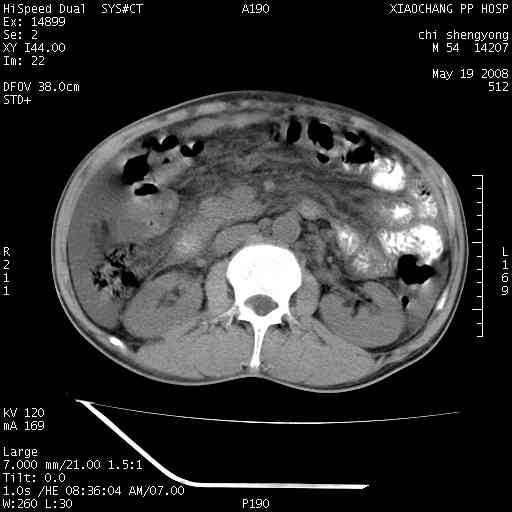

以下是引用zjzjr在2008-5-21 10:52:00的发言:[br]肝左叶巨块型肝癌伴门静脉左支瘤栓形成.肝硬化、腹水,胃底静脉曲张,脾术后改变。

以下是引用随光逐影在2008-5-21 16:20:00的发言:[br]1)肝左叶肝癌伴门静脉左支瘤栓形成,腹膜后淋巴结转移。2)肝硬化、腹水、胃底静脉曲张。3)胆囊炎。4)脾脏缺如,为切除术后所致。